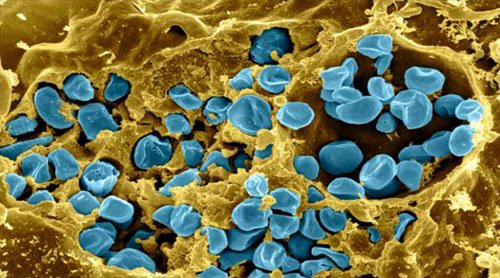

Vi khuẩn Francisella tularensis (F. tularensis) đã được sử dụng như một vũ khí sinh học từ thời Thế chiến II. Mới đây, các nhà khoa học đã sử dụng phương pháp biến đổi gen để vô hiệu hóa sự độc hại của chúng. F. tularensis gây ra một căn bệnh khó chịu gọi là tularemia, với các triệu chứng nổi bật như đau khớp, đau cơ và làm cơ thể yếu đi. Trong Thế chiến II, Hồng quân Liên Xô đã sử dụng nó để cản trở lính Đức trước trận Stalingrad.

Cho đến nay, Trung tâm Kiểm soát bệnh tật và Bảo vệ (CDC) xem F. tularensis là một trong những tác nhân khủng bố sinh học nguy hiểm nhất, cùng với bệnh than, ngộ độc, bệnh dịch hạch, bệnh đậu mùa, và sốt xuất huyết do virut. Tuy nhiên, các nhà nghiên cứu đã tìm ra cách để vô hiệu hóa loại vi khuẩn nguy hiểm này.

Bằng cách lập bản đồ mạch phân tử của vi khuẩn, các nhà nghiên cứu làm chúng không còn nguy hiểm nữa. Phương pháp này tập trung vào một nhóm các gen được gọi là “hòn đảo gây bệnh Francisella”.

Vi khuẩn gây bệnh tularemia.

Thông qua một loạt các nghiên cứu về cấu trúc, sinh hóa và tế bào, các nhà nghiên cứu đã xác định được những gen gây bệnh này được “bật” và “tắt” như thế nào. Từ đó, họ tạo ra đột biến gen khiến cho khả năng gây bệnh của vi khuẩn không thể được kích hoạt.